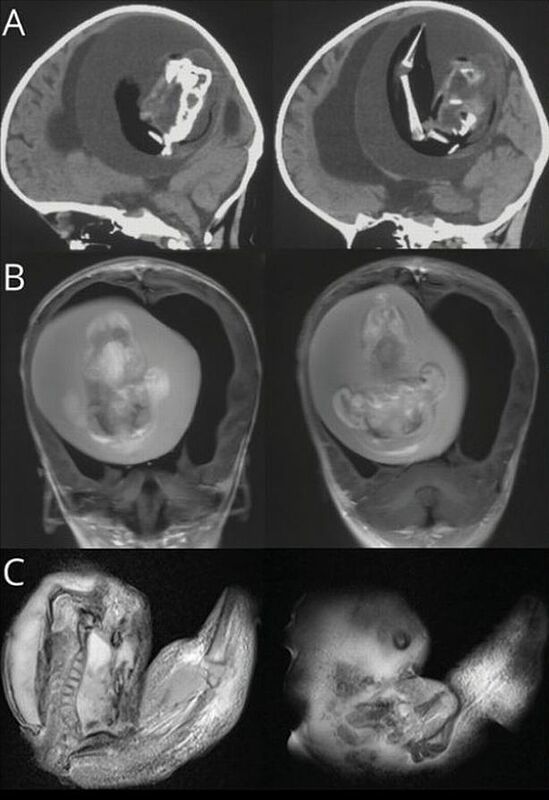

Khi thấy bé gái một tuổi đầu phình to bất thường, có vấn đề về kỹ năng vận động, khi được đưa đến bệnh viện chụp CT cho thấy một bào thai sống đang đè lên não của bé.

Bác sĩ Bệnh viện Hoa Sơn, Đại học Phúc Đán, nhận định ban đầu đây là một cặp song sinh nhưng vì lý do nào đó một thai nhi đã phát triển và bao bọc người chị em của mình. Bào thai trong đầu của bé gái tiếp tục phát triển nhiều tháng như khi còn trong bụng mẹ, đã có chi trên, xương và móng tay.

Ảnh chụp CT bào thai sống trong não bé gái.

Bác sĩ cho biết thai trong thai là hiện tượng cực kỳ hiếm gặp, thế giới chỉ ghi nhận 200 ca, trong đó 19 trường hợp bào thai cư trú ở não. Hội chứng này cũng xảy ra ở xương chậu, miệng và bộ phận sinh dục.

Thai nhi song sinh có thể phát triển nhiều tháng bên trong cơ thể người chị em, có cả cơ quan và tứ chi. Tình trạng này thường xảy ra ở các cặp song sinh cùng trứng, không thể tách rời hoàn toàn trong bụng mẹ. Đến nay, các nhà khoa học chưa biết rõ nguyên nhân dẫn đến hiện tượng kỳ lạ này.